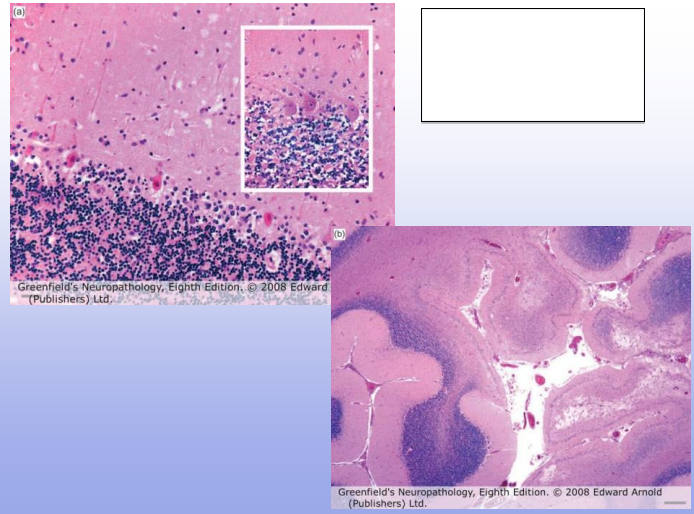

Selective neuronal cell death; brighter pink = dead, blue= normal

Infarction (left-side), Right side is normal

Global ischemic injury in cerebellum

Global cerebral Ischemia: laminar necrosis